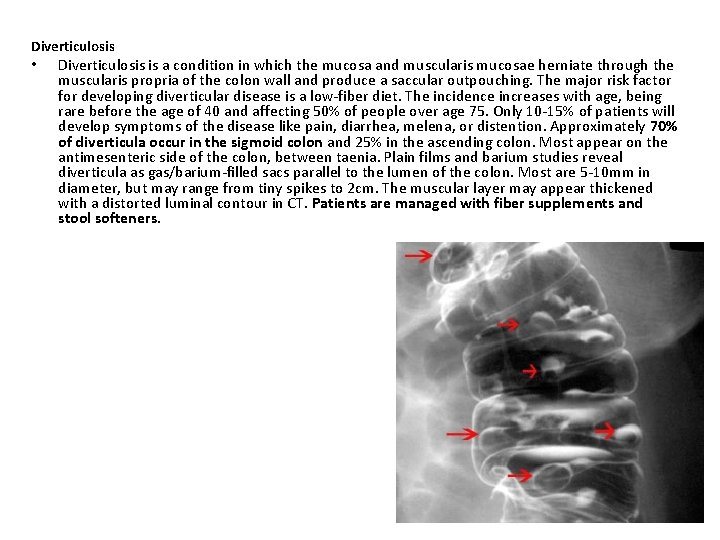

Diverticulosis • Diverticulosis is a condition in which the mucosa and muscularis mucosae herniate through the muscularis propria of the colon wall and produce a saccular outpouching. The major risk factor for developing diverticular disease is a low-fiber diet. The incidence increases with age, being rare before the age of 40 and affecting 50% of people over age 75. Only 10 -15% of patients will develop symptoms of the disease like pain, diarrhea, melena, or distention. Approximately 70% of diverticula occur in the sigmoid colon and 25% in the ascending colon. Most appear on the antimesenteric side of the colon, between taenia. Plain films and barium studies reveal diverticula as gas/barium-filled sacs parallel to the lumen of the colon. Most are 5 -10 mm in diameter, but may range from tiny spikes to 2 cm. The muscular layer may appear thickened with a distorted luminal contour in CT. Patients are managed with fiber supplements and stool softeners.